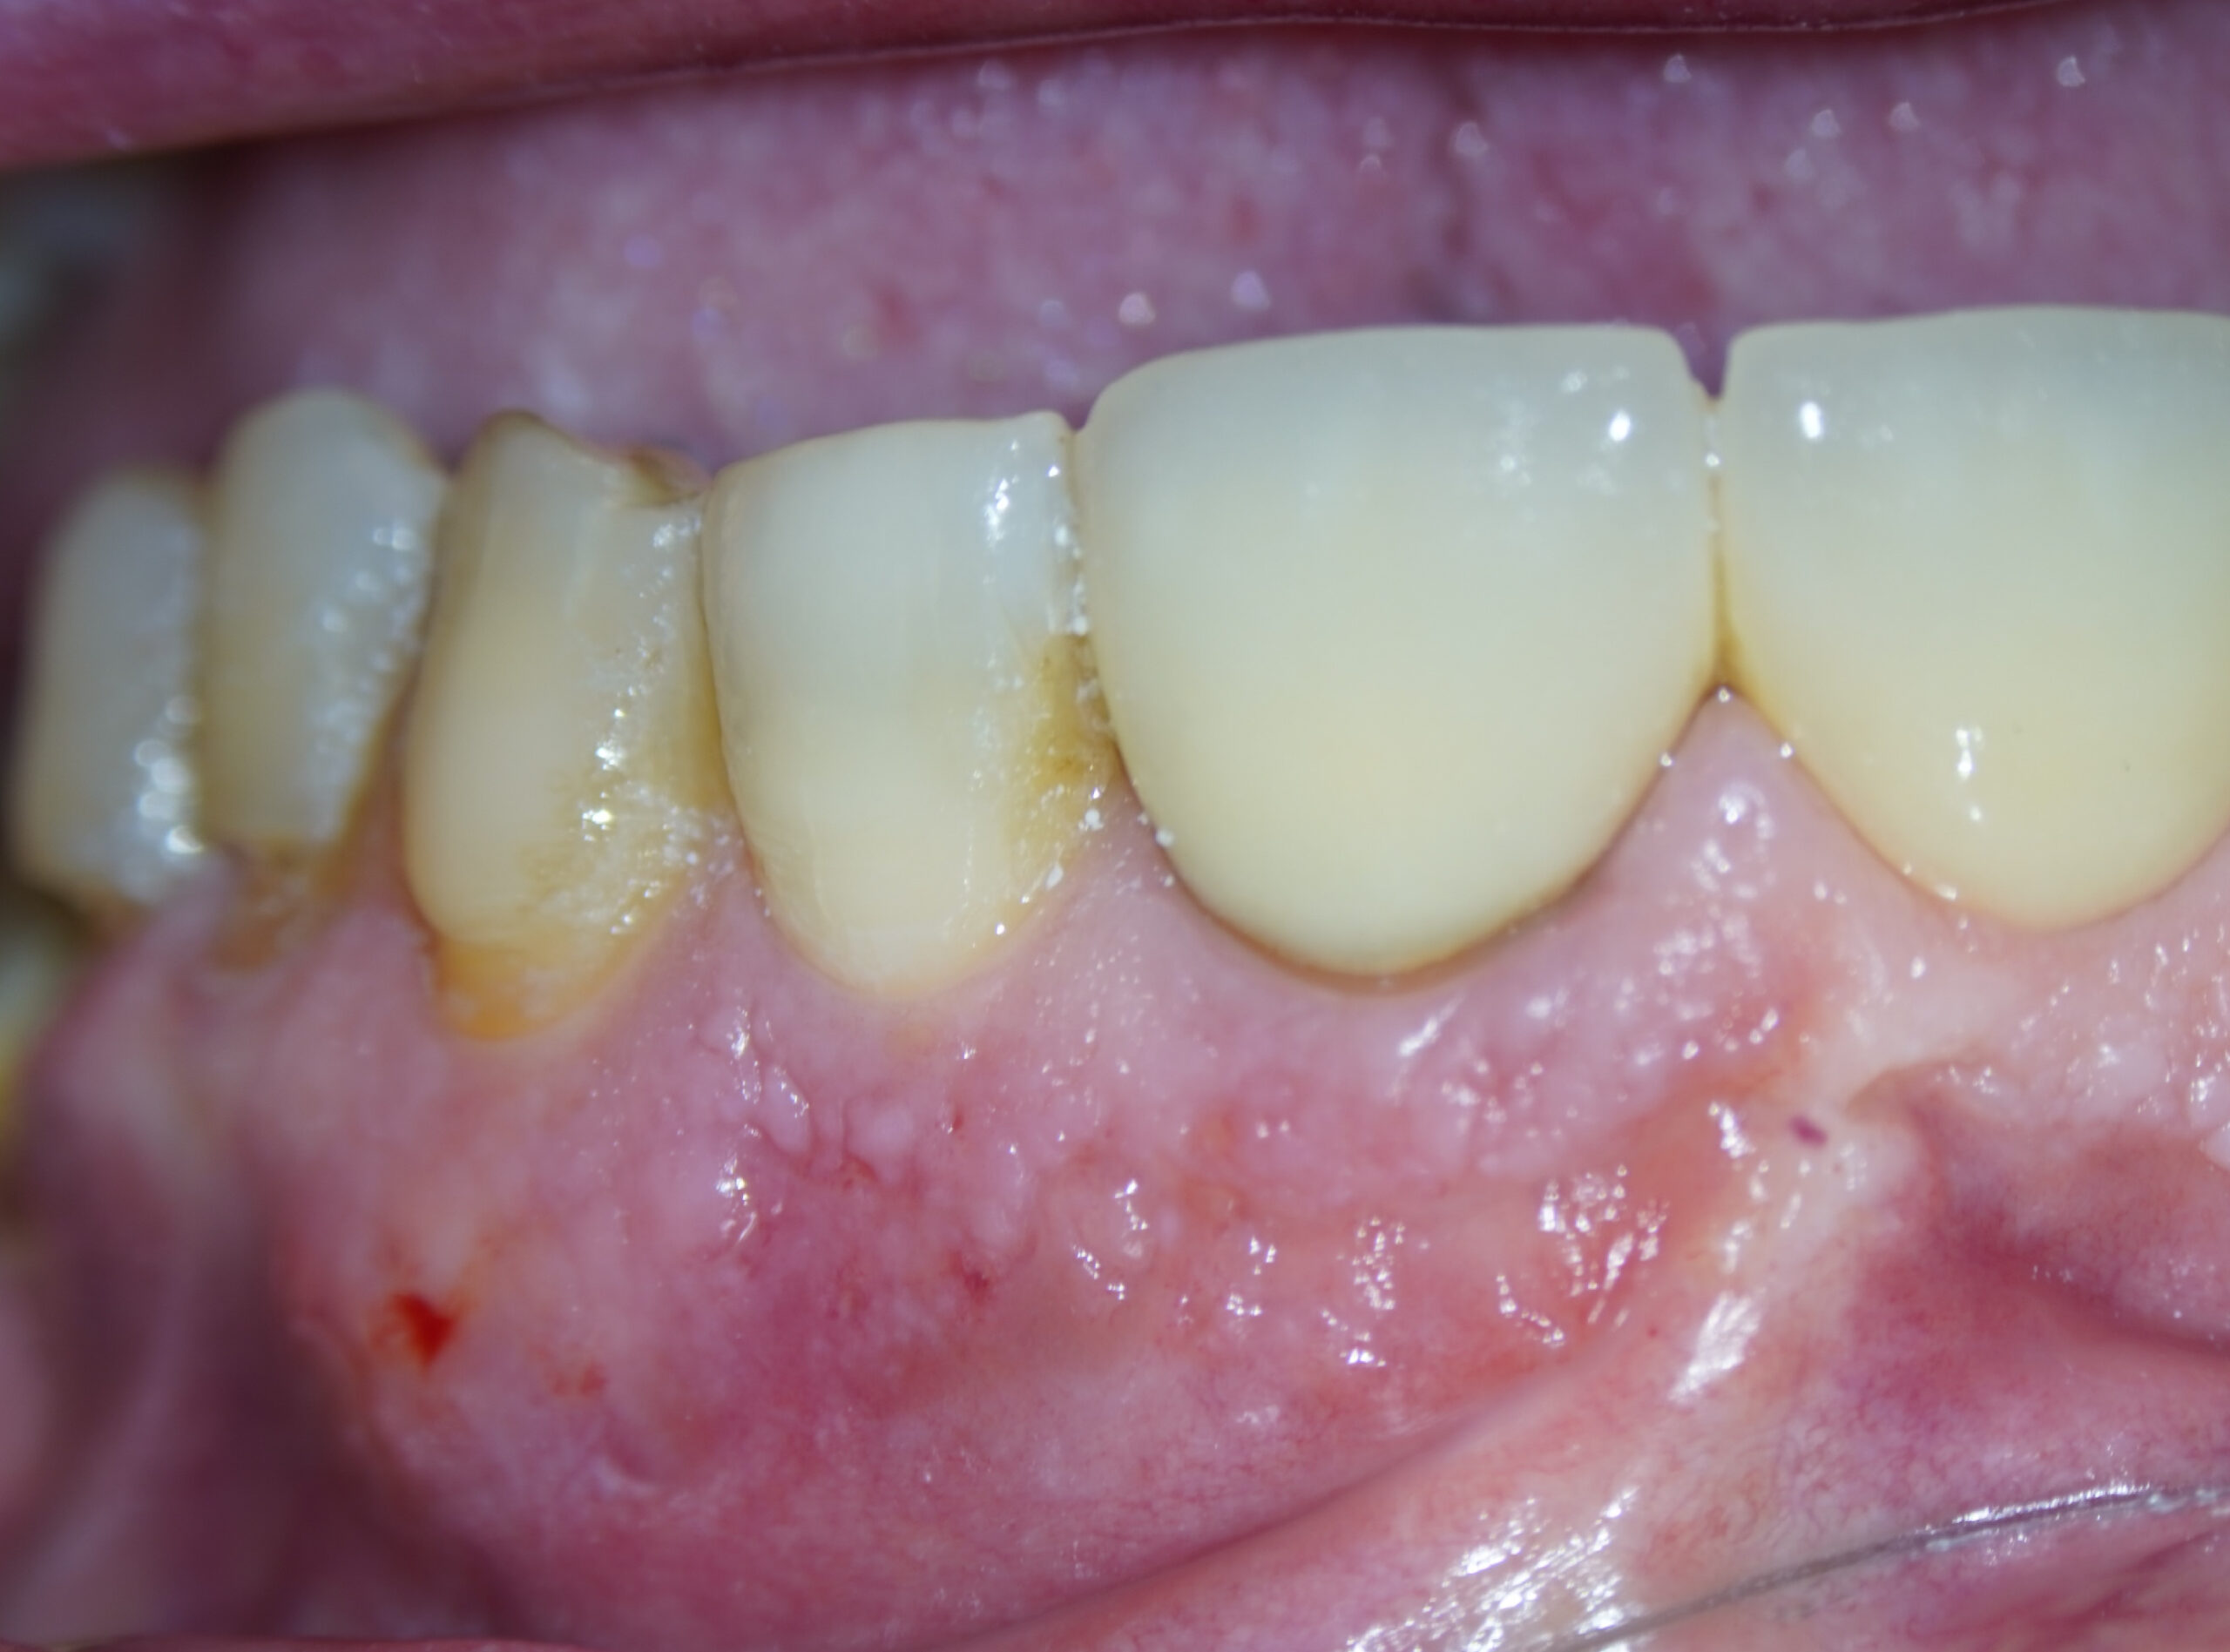

Imágenes del tratamiento

* Haz click sobre las imágenes para verlas a mayor tamaño y a color